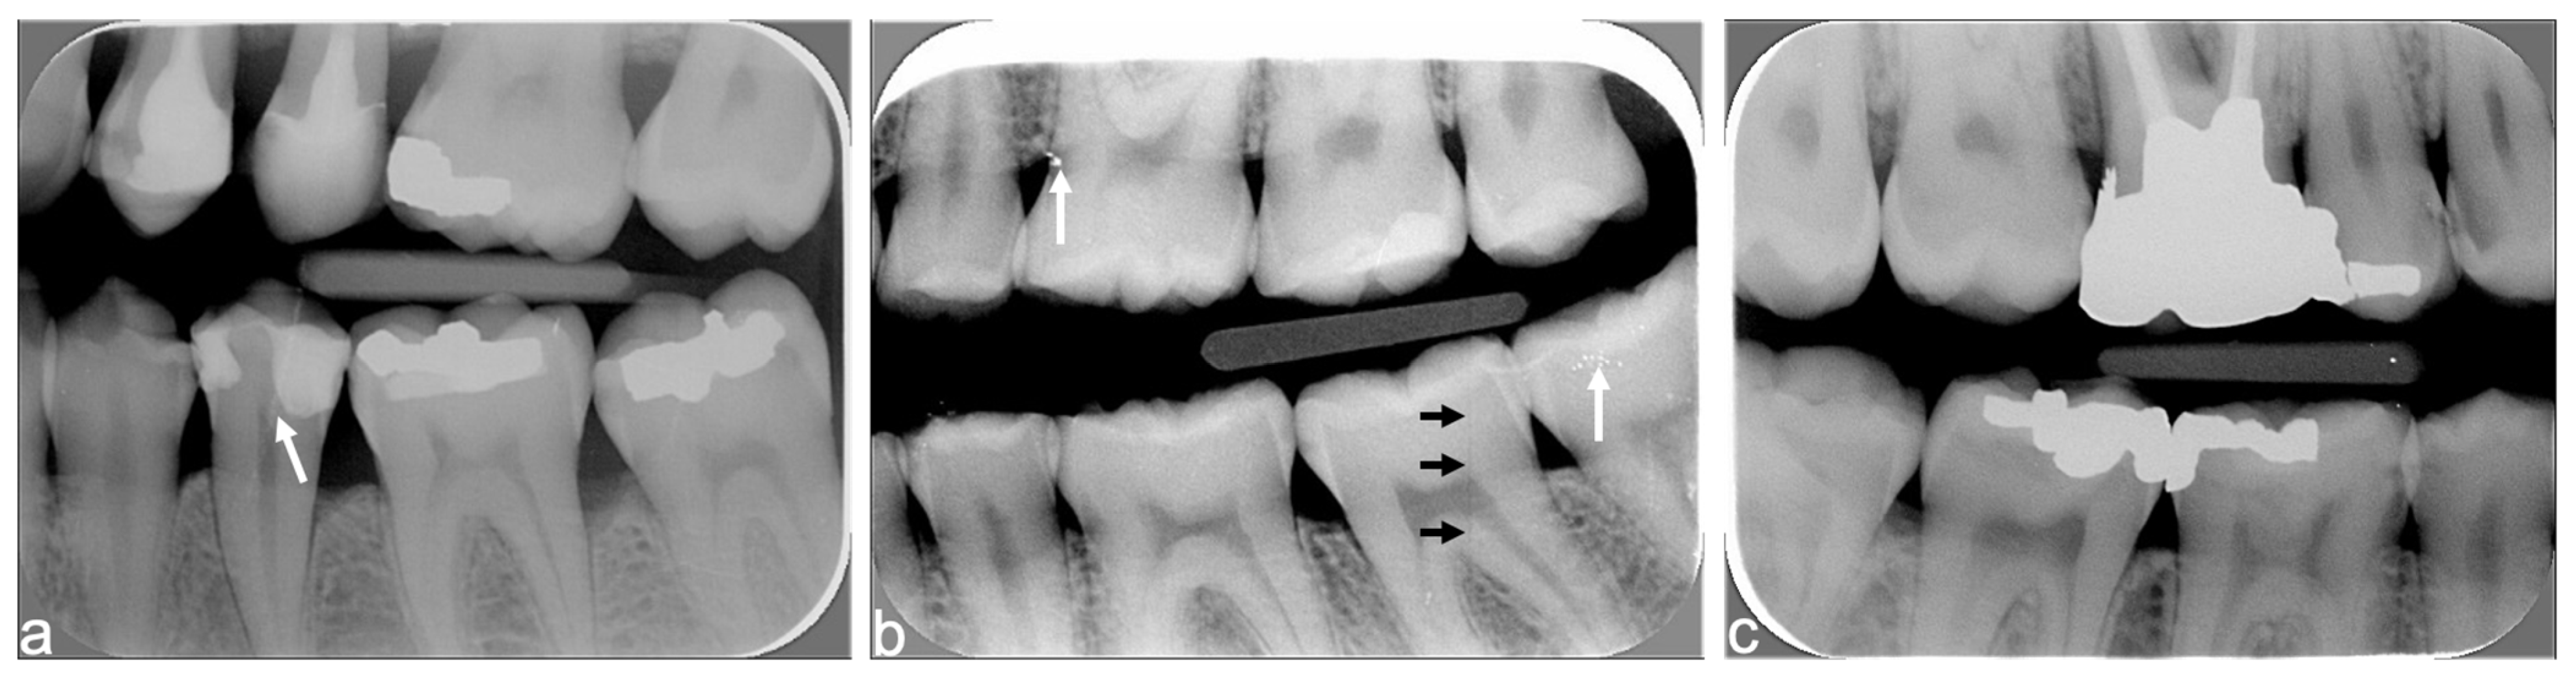

| Cone centering (with or without rectangular collimator) | Image outline Tooth fully visible | Complete image outline; borders not cut No truncated image | Incomplete image outline; image cut without consequences on diagnosis | Incomplete image outline; image cut with consequences on diagnosis |

| Centering of the digital plate | Target tooth: >2 mm of periapical bone is visible AND visible periapex of adjacent anterior tooth (size 1) or two adjacent teeth (size 2) | -- | Yes | No (one of the two parameters is not fulfilled) |

| Mesial and distal view of front tooth (size 1), or of two adjacent teeth (size 2) | -- | Yes | No | |

| Tooth fully visible (from crown to apex) | -- | Yes | No | |

| Correct bite on the film-holder | -- | Yes | No | |

| Axis of the digital plate | Correct axis of plate | -- | Yes | No |

| No vertical distortion | No distortion (absence of tooth shortening or lengthening) | -- | Yes | No |

| Image contrast | Correct image contrast | -- | Yes | No (too bright or too dark) |

| Artefacts | Exposure to ambient light, presence of foreign object or vertical stripes | -- | No Or minimal without consequence on diagnosis | Yes With consequence on diagnosis |

| Intact digital plate, without traces of scratches, folds, or other | -- | No Or minimal without consequence on diagnosis | Yes With consequence on diagnosis | |

| Overall X-ray quality | Overall quality | Excellent overall quality | Acceptable quality; minor errors | Major error; interpretation is difficult |